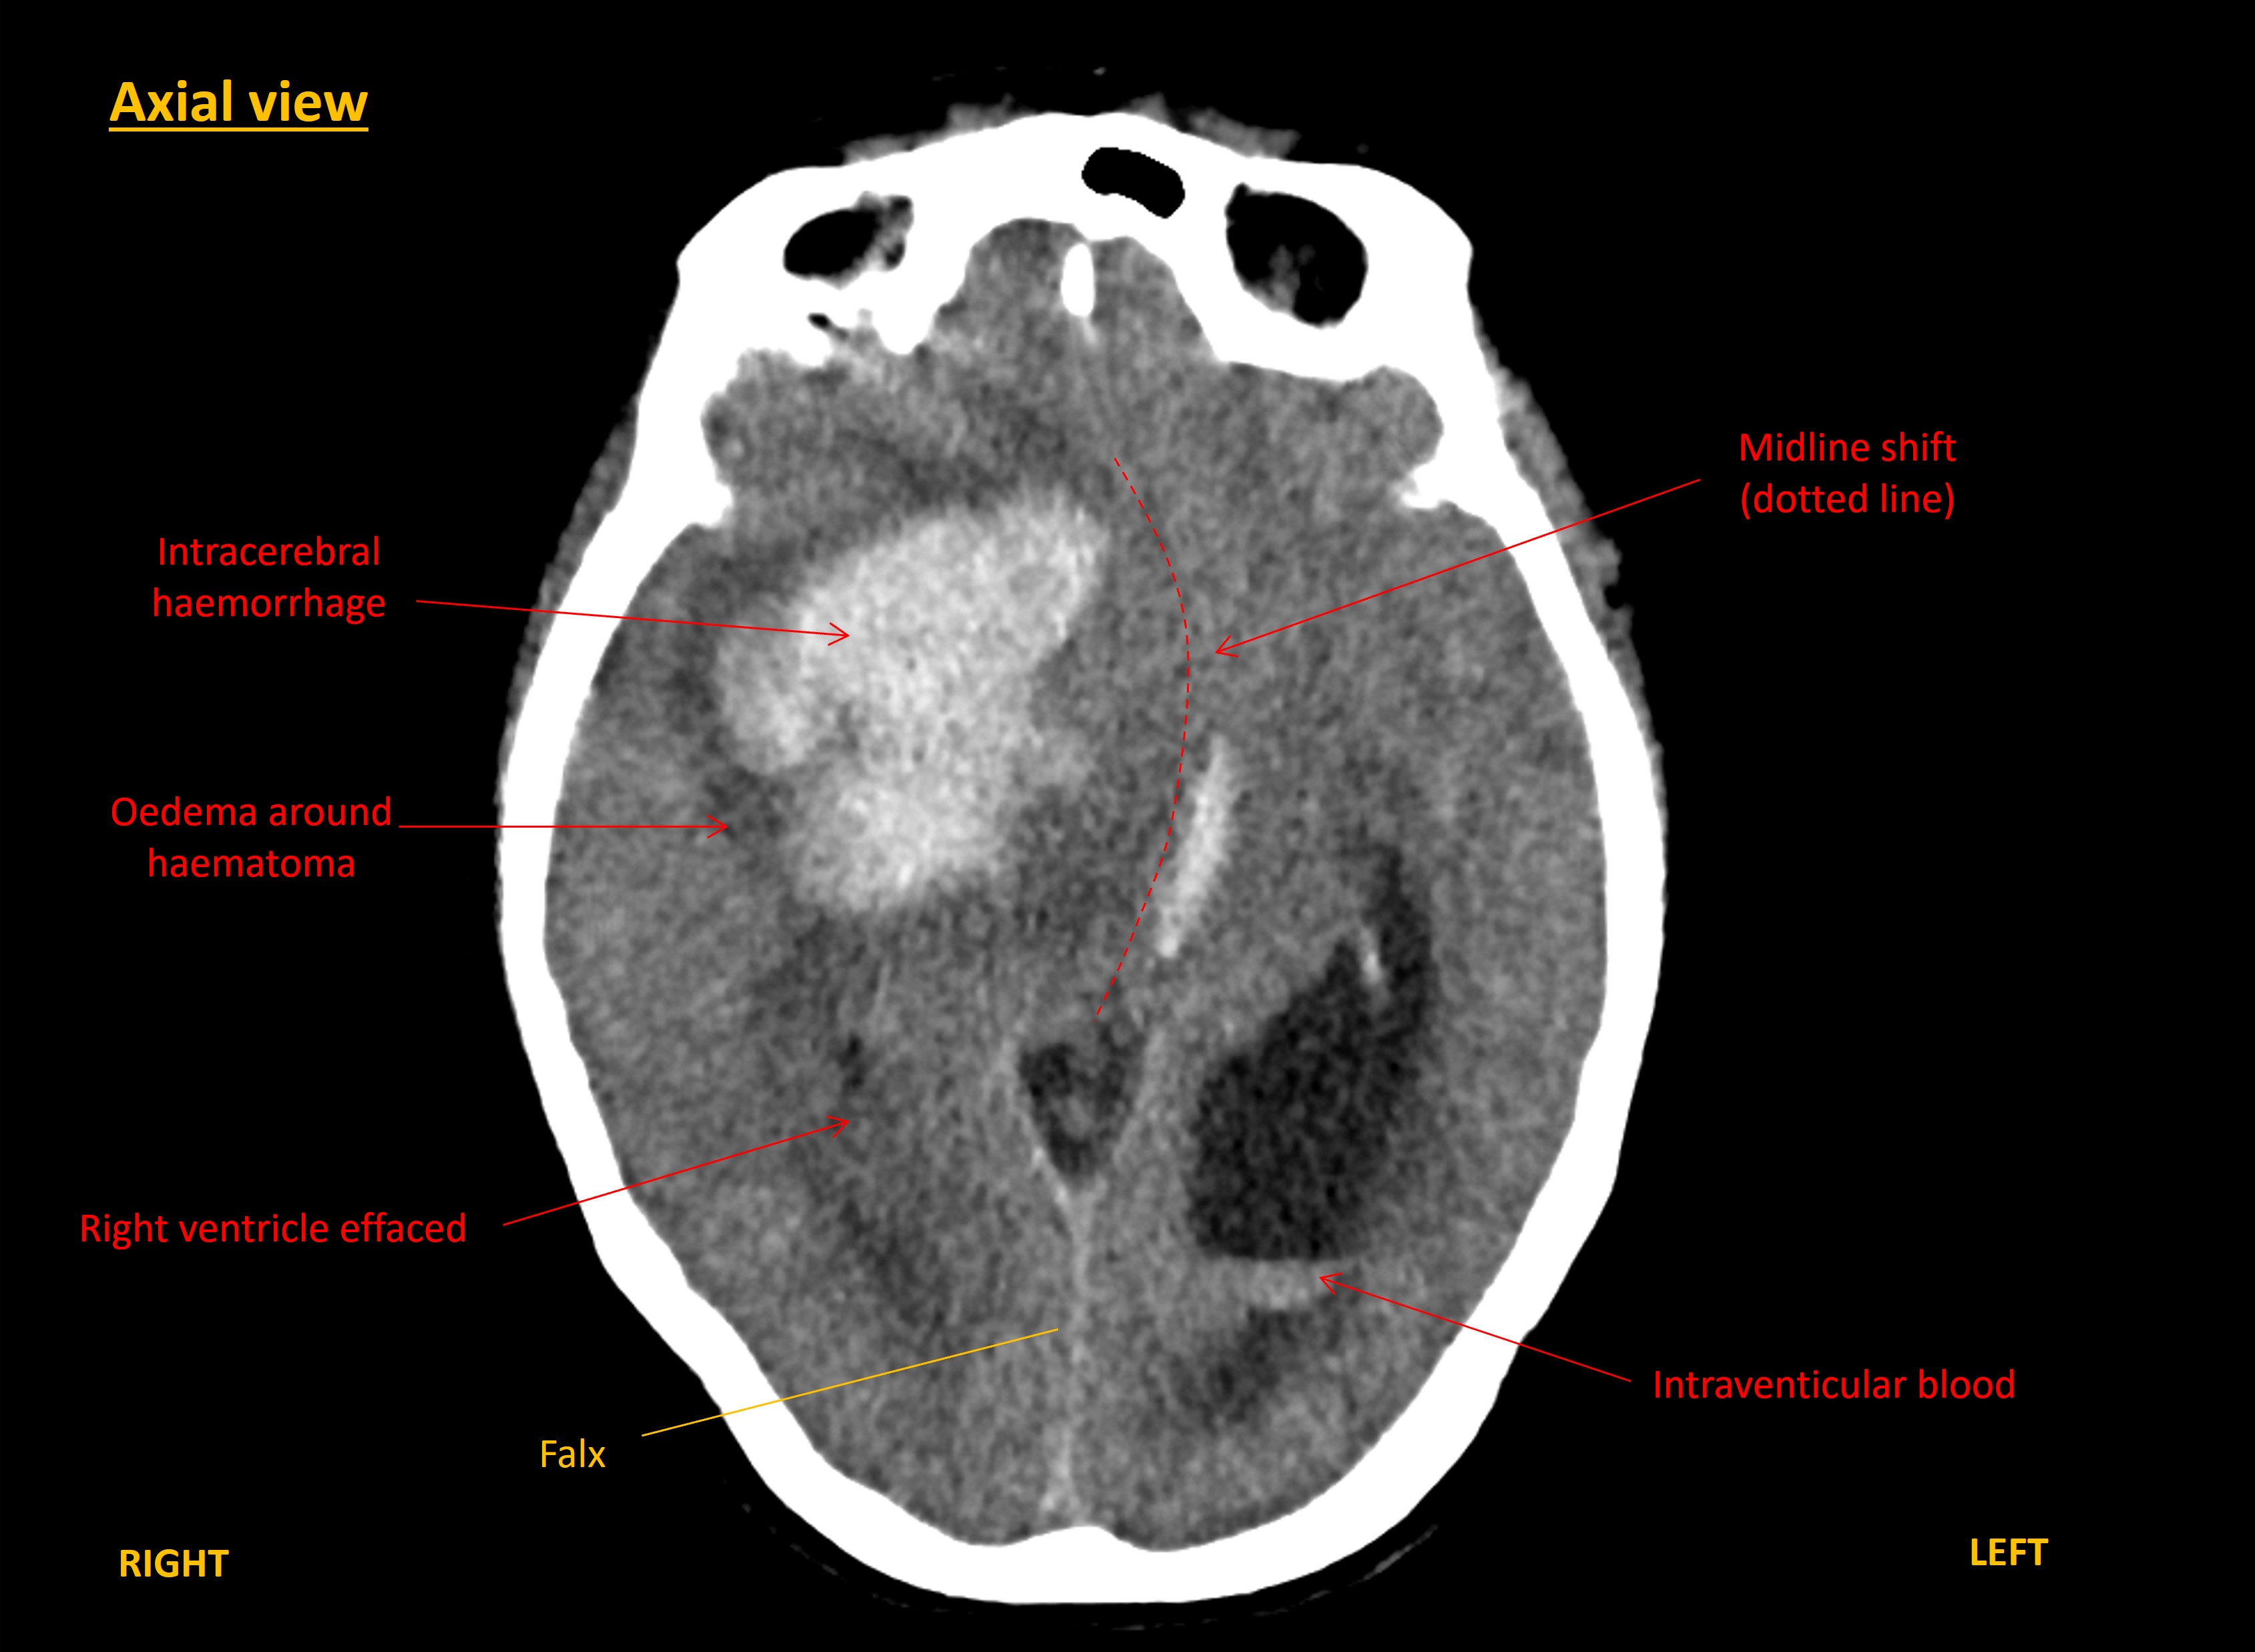

A CT brain was performed immediately. This showed a large right-sided intracerebral haemorrhage within the frontal and parietal lobes. The blood was causing mass effect with midline shift towards the left, and right uncal herniation. The haemorrhage had extended into the ventricles, including down to the fourth ventricle, with hydrocephalus.